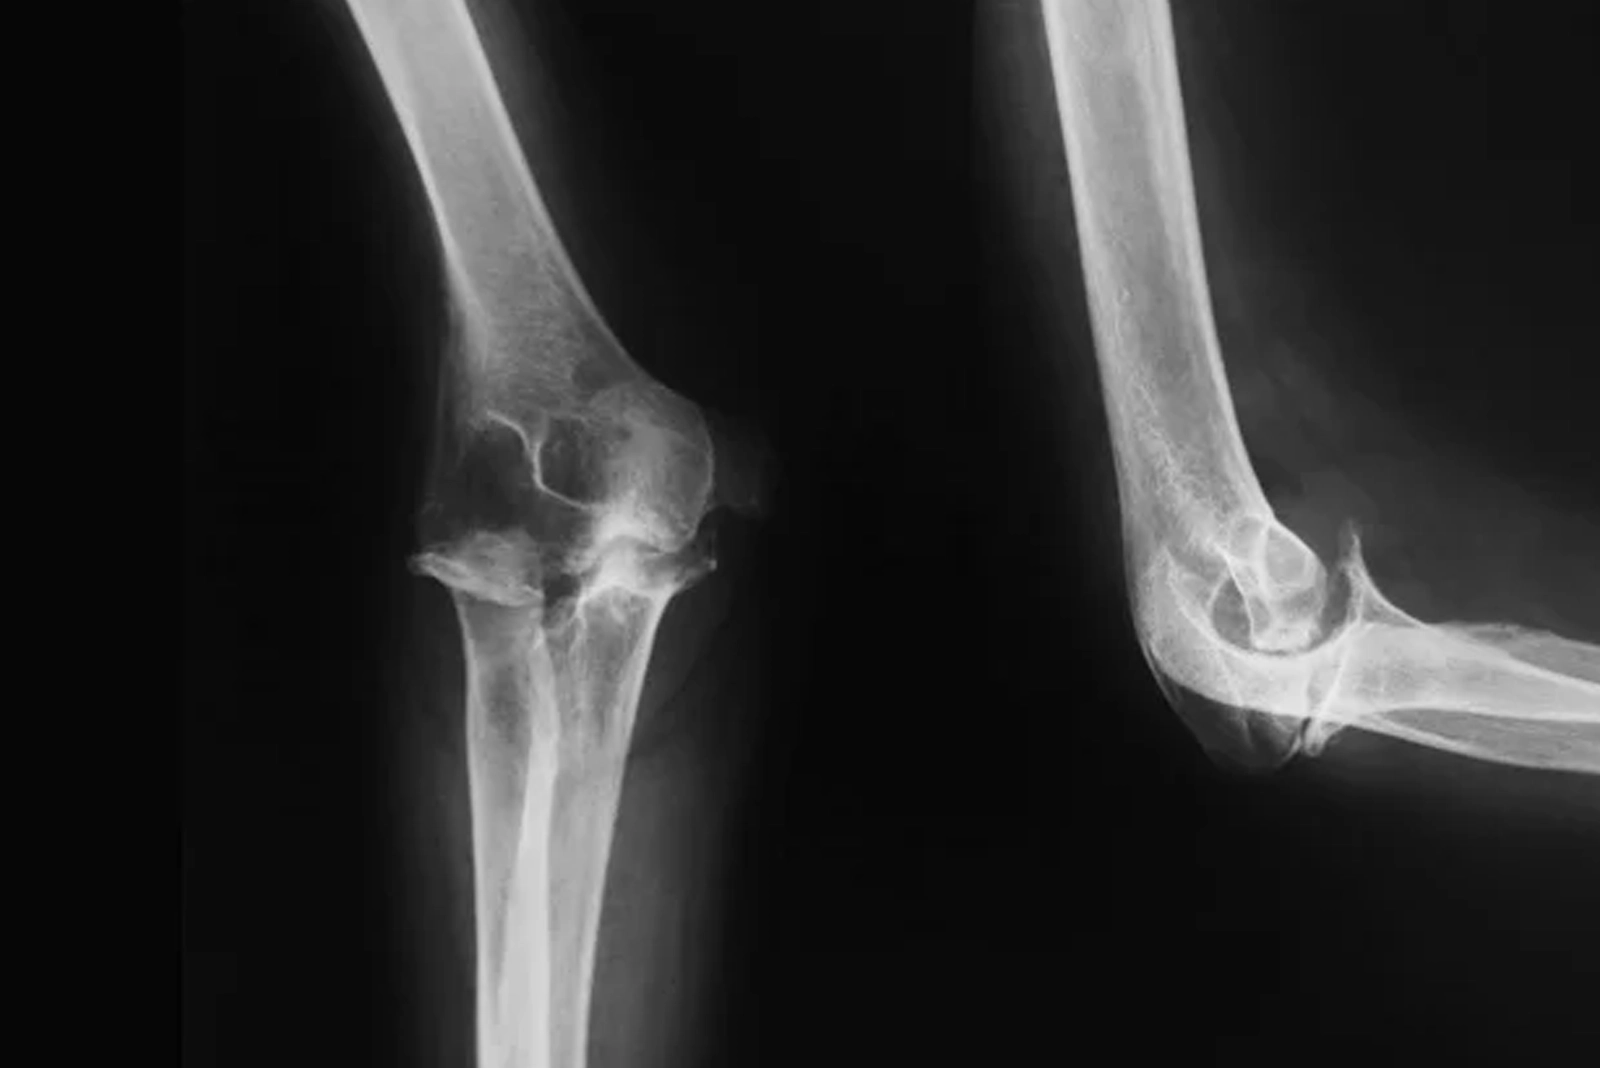

Diagnosis of Elbow Pain

An accurate diagnosis is essential to guide treatment. At Alleviate Pain Clinic, we use advanced diagnostic tools to pinpoint the root cause and offer a non-surgical elbow pain treatment option.